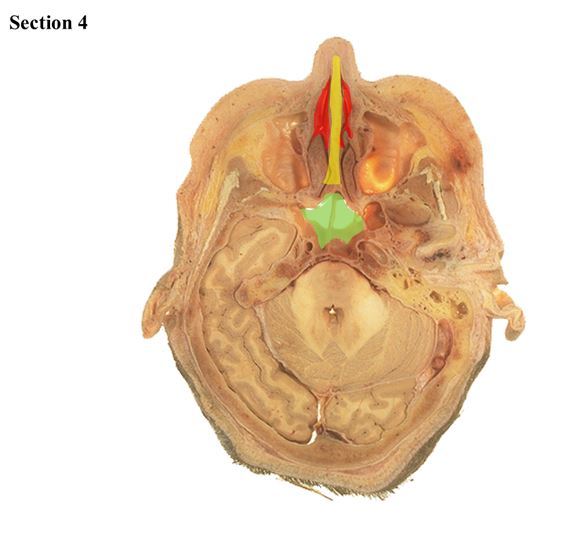

4

Q

The orange bone is the _____

The red structure anterior to the ear is the _____

A

mandible

parotid salivary gland

How well did you know this?